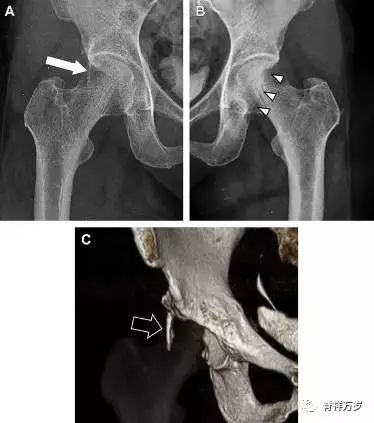

髋臼骨折最常见的类型是髋臼后壁骨折,几乎占髋关节骨折的 1/4,且常常合并髋关节后脱位。由于骨性结构重叠,可能肉眼看上去觉得非常轻微的骨折,事实却并非如此。髋臼后缘中断常常是髋臼后壁骨折的一个特征(图 1)。

图 1 为髋臼后壁骨折伴髋关节脱位患者。A 右侧髋关节 X 线片示股骨头后方可见一骨折线(箭头),髋臼后缘中断。B 左侧髋关节 X 片对照可见髋臼后缘连续(箭头)。C CT 三维重建图像示髋臼后壁缺损,可见旋转、移位的骨折块(箭头)